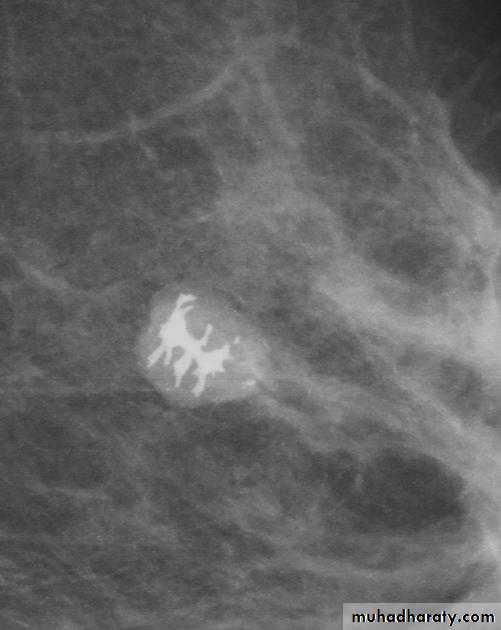

Micro calcifications

Micro calcifications are tiny specks of calcium in the breast. Micro calcifications seen on a mammogram are of more concern than macrocalcifications, but they do not always mean that cancer is present. The shape and layout of microcalcifications help the radiologist judge how likely it is that cancer is present.

In most cases, the presence of microcalcifications does not mean a biopsy is needed. But if the microcalcifications have a suspicious look and pattern, a biopsy will be recommended. (During a biopsy, the doctor removes a small piece of the suspicious area to be looked at under a microscope. A biopsy is the only way to tell if cancer is really present.)

A mass it is calcification & margin

>>>>>> A mass will detected>>>>>> if it is with or without calcifications, change seen on a mammogram.

>>>>>> it is Margin